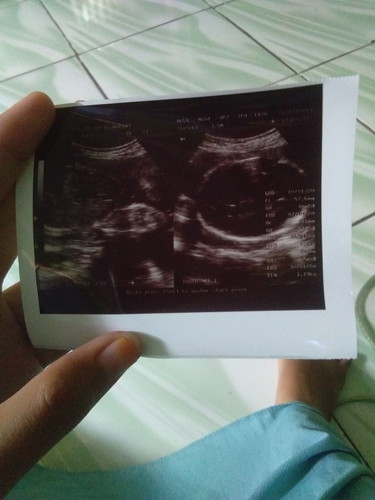

30week

Bunda normal ga yah 30wk bb janinnya 1,19gram ?

Kyaknya kecil bun. Di aplikasi hrusnya brpa kg bun?